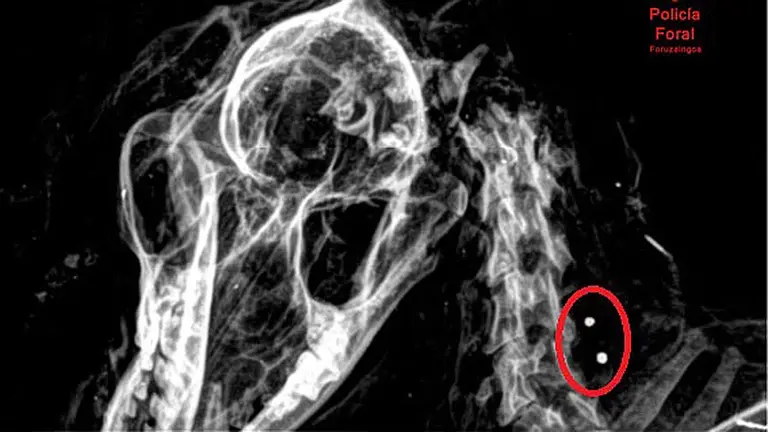

Un remanso de paz en medio del mundanal ruido de la capital. Así viven los tres centenares de animales del minizoo del parque de la Taconera de Pamplona. Entre las murallas y decenas de especies arbóreas, acostumbrados a la presencia del ser humano en sus vida, aunque sea a varios metros de altura. Estas son algunas de las mejores imágenes que vas a ver de ellos desde dentro del foso en el que conviven. Puedes leer el reportaje completo aquí: Un día en el mini zoo de la Taconera en Pamplona: la vida de 320 animales dentro de los fosos